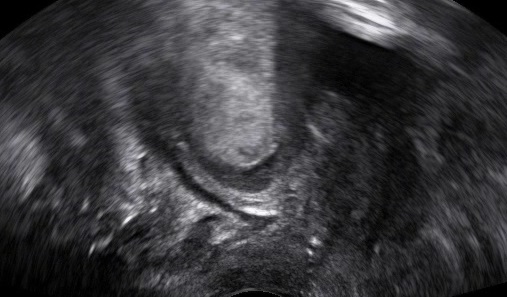

An enterocele refers to the caudal displacement of small bowel loops. Τhe enterocele typically appears in the posterior vaginal wall, but not exclusively. Rarely it might also appear in the anterior vaginal wall. In post-hysterectomy patients the enterocele sac descends through the middle, displacing the vaginal cuff caudally. Differentiating the enterocele from a rectocele and other types of prolapse is essential for proper surgical planning.

Depicting an enterocele in pelvic floor ultrasound is feasible: